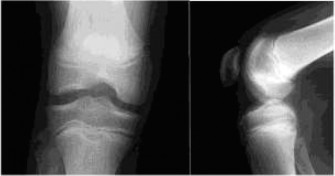

CASE 15 A 12-year-old male presents to the orthopaedic clinic with several mont…